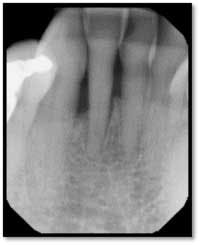

Pockets 4-9mm Class ll furcation involvement in both molars, possible endo abscess #3, (tooth is asymptomatic)

LR Pre TxPockets: 4-8mm

A full set of radiographs taken 13 months post therapy show bone fill in the deepest pockets, with generalized pocket reductions of up to 7mm.